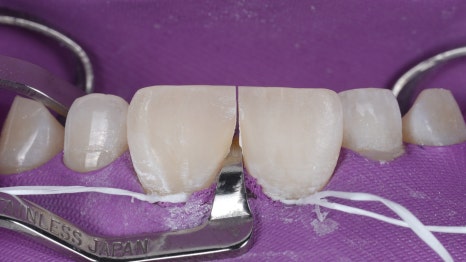

촬영일 : 251121

러버댐을 장착하고 Unica Proximal을 사용하여 레진으로 앞니 사이 모양을 디자인하면서 형태를 잡아줬습니다.

마무리로 아주 얇은 연마 기구(soflex)를 활용하여 매끄럽게 다듬어 드렸죠.

벌어진 사이가 자연스럽게 메워진 것을 볼 수 있었어요.